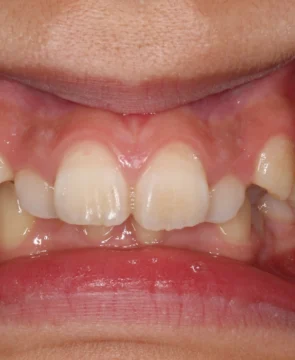

2026/04/14全体的な歯並びのがたつきが気になる10歳女児の矯正症例紹介 今回ご紹介する患者様は、全体的な歯並びのがたつきを気にされており、矯正検査後叢生Ⅰ級と診断いたしました。 治療前後の比較 矯正術前:正面 矯正術後:正面 矯正術前:右側 矯正術後:右側 矯正術前:左側 矯正術後:左側 矯正術前:上顎 矯正術後:上顎 矯正術前:下顎 矯正術後:下顎 矯正術前:前歯部あおり 矯正術後:前歯部あおり 矯正術前:オーバージェット 矯正術後:オーバージェット 主訴 全体的な歯並びのがたつきが気になる 治療期間 ・マウスピース矯正:10カ月 治療費用 …